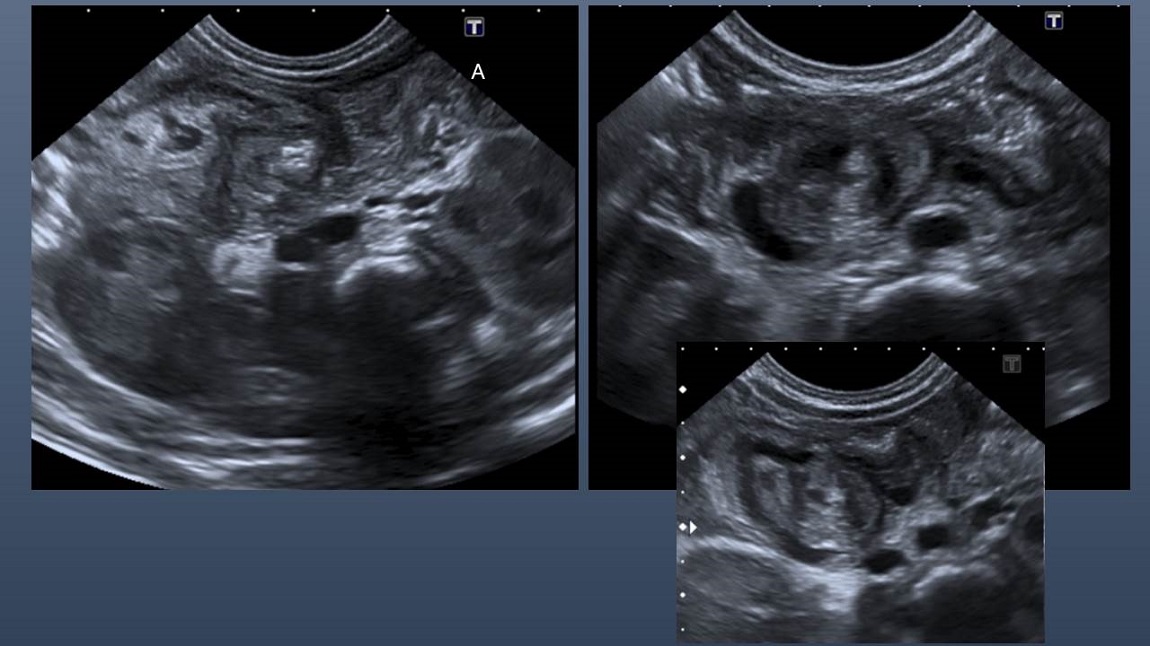

Teniendo en cuenta los hallazgos inespecíficos de la radiografía de abdomen y ante el empeoramiento clínico de la paciente, con incremento de los vómitos biliosos e ictericia de predominio indirecto, se solicita ecografía abdominal. Con la imagen ecográfica. ¿Cuál es su sospecha diagnóstica?

Se visualizan las siguientes tres imágenes ecográficas.